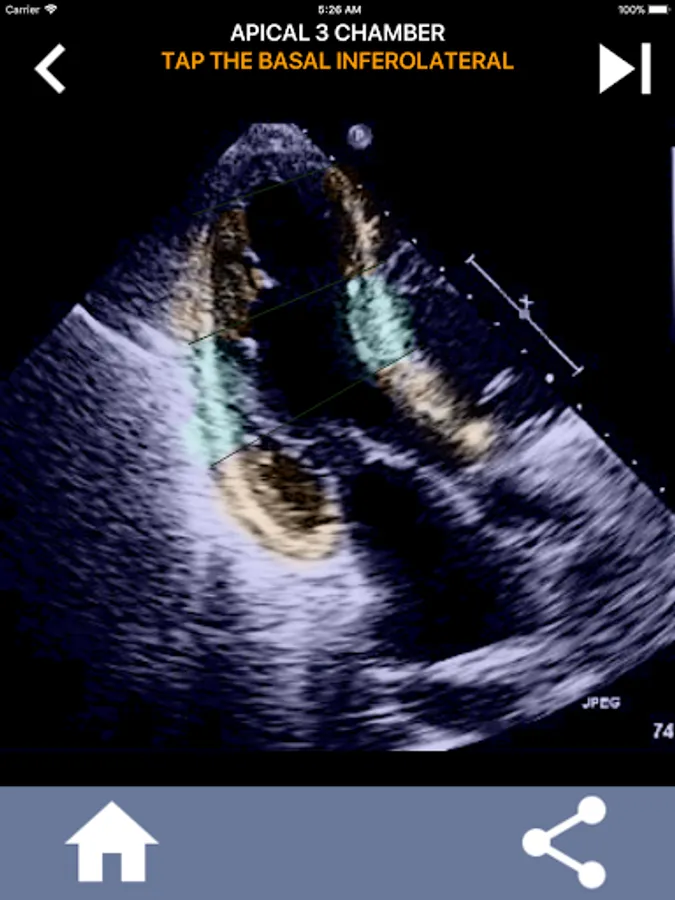

Understanding the AHA (American Heart Association) heart segments is of utmost importance for a cardiac sonographer to effectively communicate with the cardiologist who writes the report. By knowing the specific anatomical regions and their corresponding segments, the sonographer can accurately describe and communicate any abnormalities or findings, ensuring clear and concise communication between both professionals.

This understanding becomes particularly crucial when the cardiologist seeks to ascertain the precise location of a problem or when the on-call physician identifies an issue within a specific region, prompting the sonographer to accurately display the corresponding segment, such as the mid-inferior wall. Thus, possessing a comprehensive grasp of the AHA heart segments is essential skill set.

This app will test your knowlegde using actual echo images, which I often find to be the best teaching method.